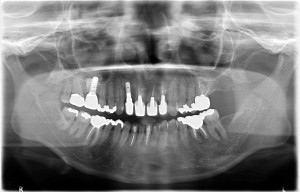

術後レントゲン写真

-